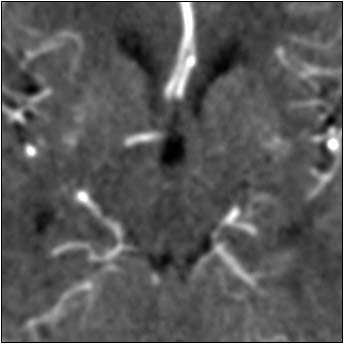

| Top image: original CT perfusion data shows brain parenchyma and opacified blood vessels (white), as well as substantial image noise. Middle image: same CT data after Gaussian filtering, which reduces image noise, but also reduces signal intensity in the blood vessels and distorts the signal in areas surrounding the vessels. Bottom image: Same data following application of anisotropic filter, which reduces image noise while preserving tissue boundaries. The boundaries are preserved by elongating the filter in a parallel orientation with the edges, such that the filter remains sufficiently large for appropriate noise reduction, but avoids mixing of several tissue types. All images courtesy of Marcel Quist. |